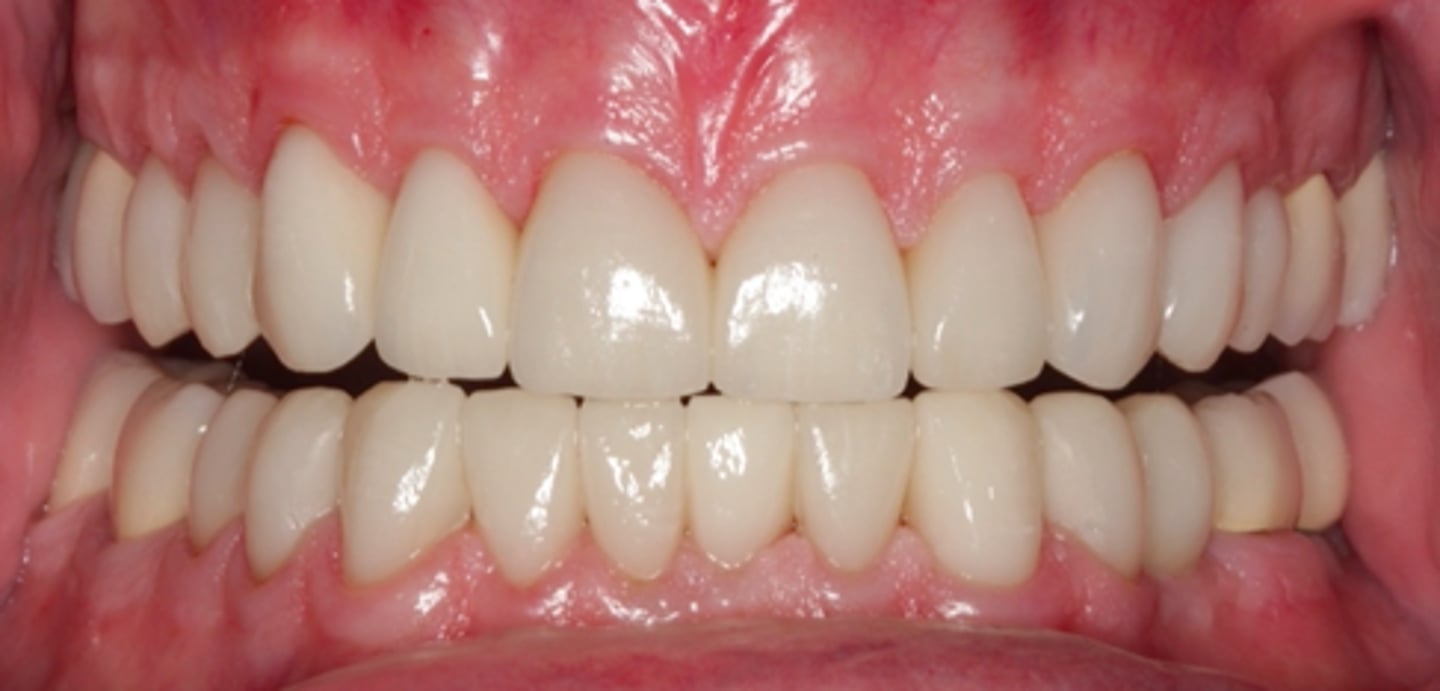

<p>what class is this picture?</p>

what class is this picture?

class III